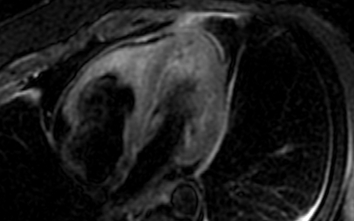

A middle-aged man with a history of asthma and chronic sinusitis presented with pleuritic chest pain, breathlessness, and numbness in his left arm. On examination, he was hypertensive, tachypneic, and hypoxic. Laboratory workup showed leukocytosis with marked eosinophilia (13.09 x 10^3/μL), elevated cardiac biomarkers, and proteinuria. Computed tomography angiography revealed subsegmental pulmonary embolism. Echocardiography showed a moderately dilated right ventricle with reduced systolic function. Cardiac imaging identified diffuse myocardial edema, subendocardial enhancement in the right ventricle, and an apical thrombus. Cerebral magnetic resonance imaging revealed multifocal diffusion-restricted lesions. Coronary angiography showed no obstructive disease. Given the constellation of asthma, eosinophilia, neuropathy, and sinus disease, eosinophilic granulomatosis with polyangiitis (EGPA) was strongly considered. Testing for clonal eosinophilic syndromes and antineutrophil cytoplasmic antibodies was negative. Immunosuppressive therapy, including Rituximab and Mepolizumab, was initiated. Follow-up imaging at 9 months demonstrated complete resolution of myocardial inflammation and thrombus.

Cardiac involvement in eosinophilic granulomatosis with polyangiitis is a major determinant of morbidity and mortality, contributing to nearly half of EGPA-related deaths. Clinical manifestations may include myocarditis, pericarditis, heart failure, or intracardiac thrombus. However, cardiac EGPA often lacks classic ischemic findings, making diagnosis challenging. Cardiac magnetic resonance imaging is the most sensitive modality for detecting myocardial inflammation, subendocardial fibrosis, and mural thrombus, particularly when endomyocardial biopsy is contraindicated. In this case, cardiac magnetic resonance imaging provided critical diagnostic clarity, revealing diffuse myocardial edema and subendocardial enhancement, features consistent with eosinophilic myocarditis. Integration of imaging findings with peripheral eosinophilia, asthma, neuropathy, and sinus disease enabled the timely recognition of EGPA. This case underscores the importance of early, multimodal cardiac imaging in patients with unexplained cardiac dysfunction and eosinophilia to prevent irreversible damage through targeted immunosuppression.